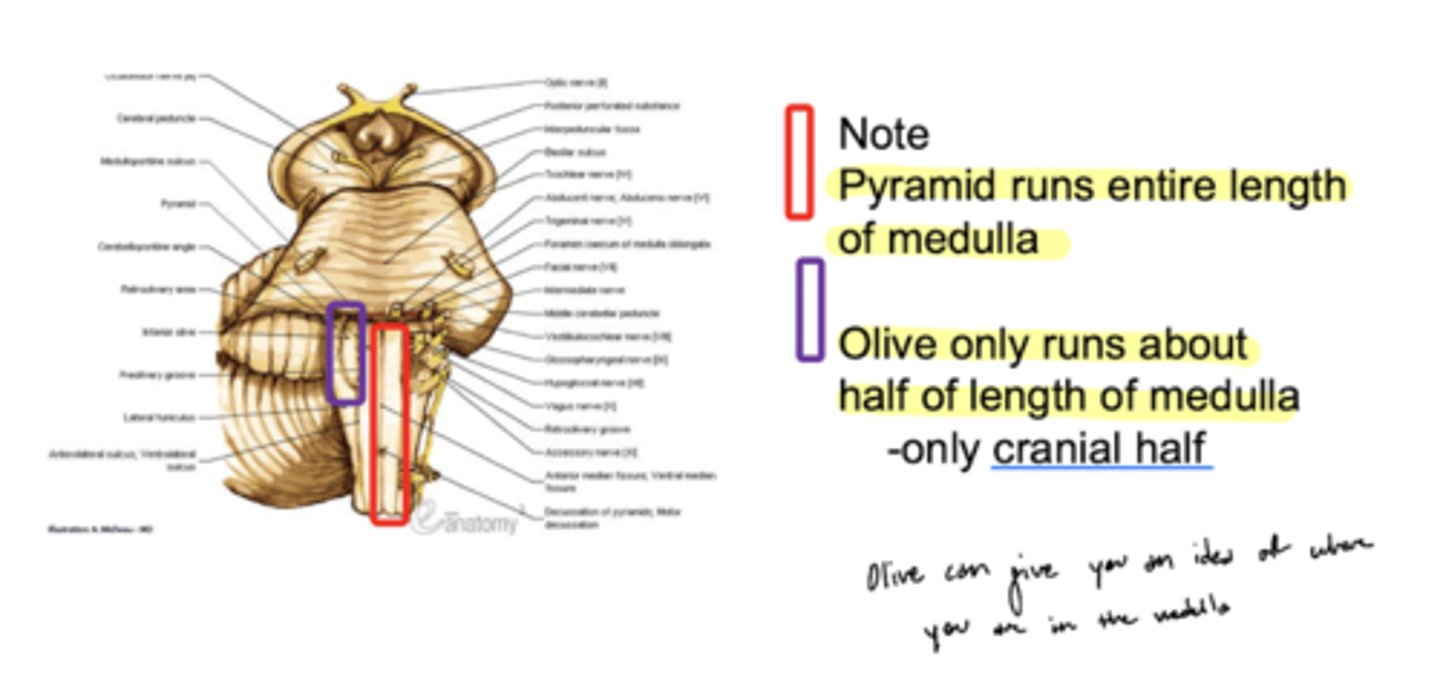

What are the structures of the ventral medulla oblongata (medial to lateral)?

1. pyramid

2. olive

3. lateral funiculus

What divides the right and left pyramid of the medulla oblongata?

anterior median fissure

What divides the pyramid from the olive of the medulla oblongata?

anterior lateral sulcus

What divides the olive and lateral funiculus?

posterolateral sulcus

Do the pyramids run the entire length of the medulla oblongata?

yes

Does the olive (right and left) run the entire length of the medulla oblongata?

no -- only half (cranial)